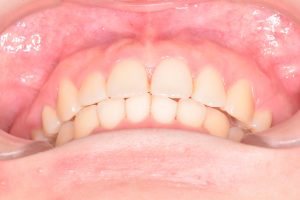

正面

0000000007

0000000135